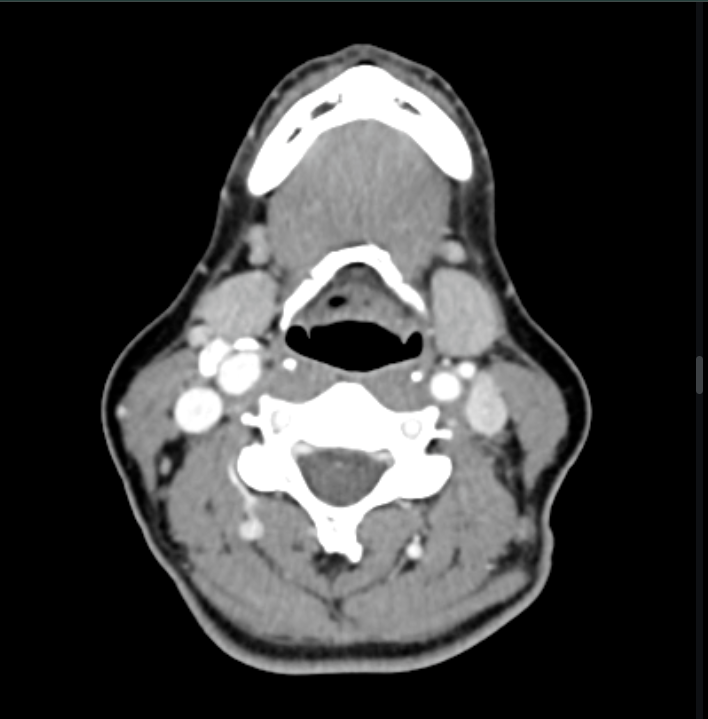

Neck pain and swelling

Diagnosis: Medullary thyroid cancer

Certainty: Almost Certain

Author: Ahmad Salim

Date Published: Sep 2, 2025

Disease Specialty: Oncology

Image Type:

CT Scan